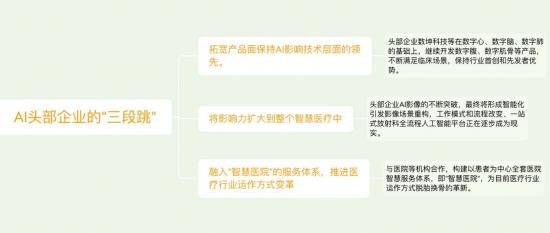

三 原创AI企业“马太效应”明显,行业趋势迈向整体解决方案

从AI影像行业的发展特别是融资结构来看,头部企业已经进入市场认可、商业模式成熟、技术护城河建立的阶段,尾部企业的追赶愈加艰难,医疗影像AI行业的“马太效应”初步显现,其野心正在逐渐扩展到整个AI+医疗甚至智慧医院层面。

在此核心逻辑的支撑下,原创AI影像头部企业正在尝试“三段跳”。

当然,一口吃不下一个胖子,目前,AI影像行业企业大多集中在“第一跳”,头部企业数坤科技等可能实现了“第二跳”,距离“智慧医院”的阶段还有相当长的一段路要走。但无论如何,由原创AI智慧影像作为突破点,将使适用场景扩展到医疗体系的方方面面,AI赋能医疗行业更好的为患者服务的宏伟蓝图已经徐徐展开。

试问谁能在智慧医疗领域逐鹿中原?唯有在AI影像领域拥有极致技术流,且极度爱医疗、懂医疗、懂医生的原创拓荒者,方能给出答案。